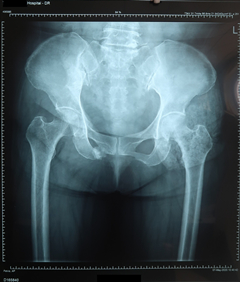

(1)三维CT片(某某医院,CTXXXXXXXX,2019-10-27):右侧髂骨、耻骨上下支骨皮质断裂,髂骨骨折线累及骶髂关节,骶髂关节间隙略增宽,断端错位成角,可见碎骨片。

图1.三维CT片(CTXXXXXXXX)